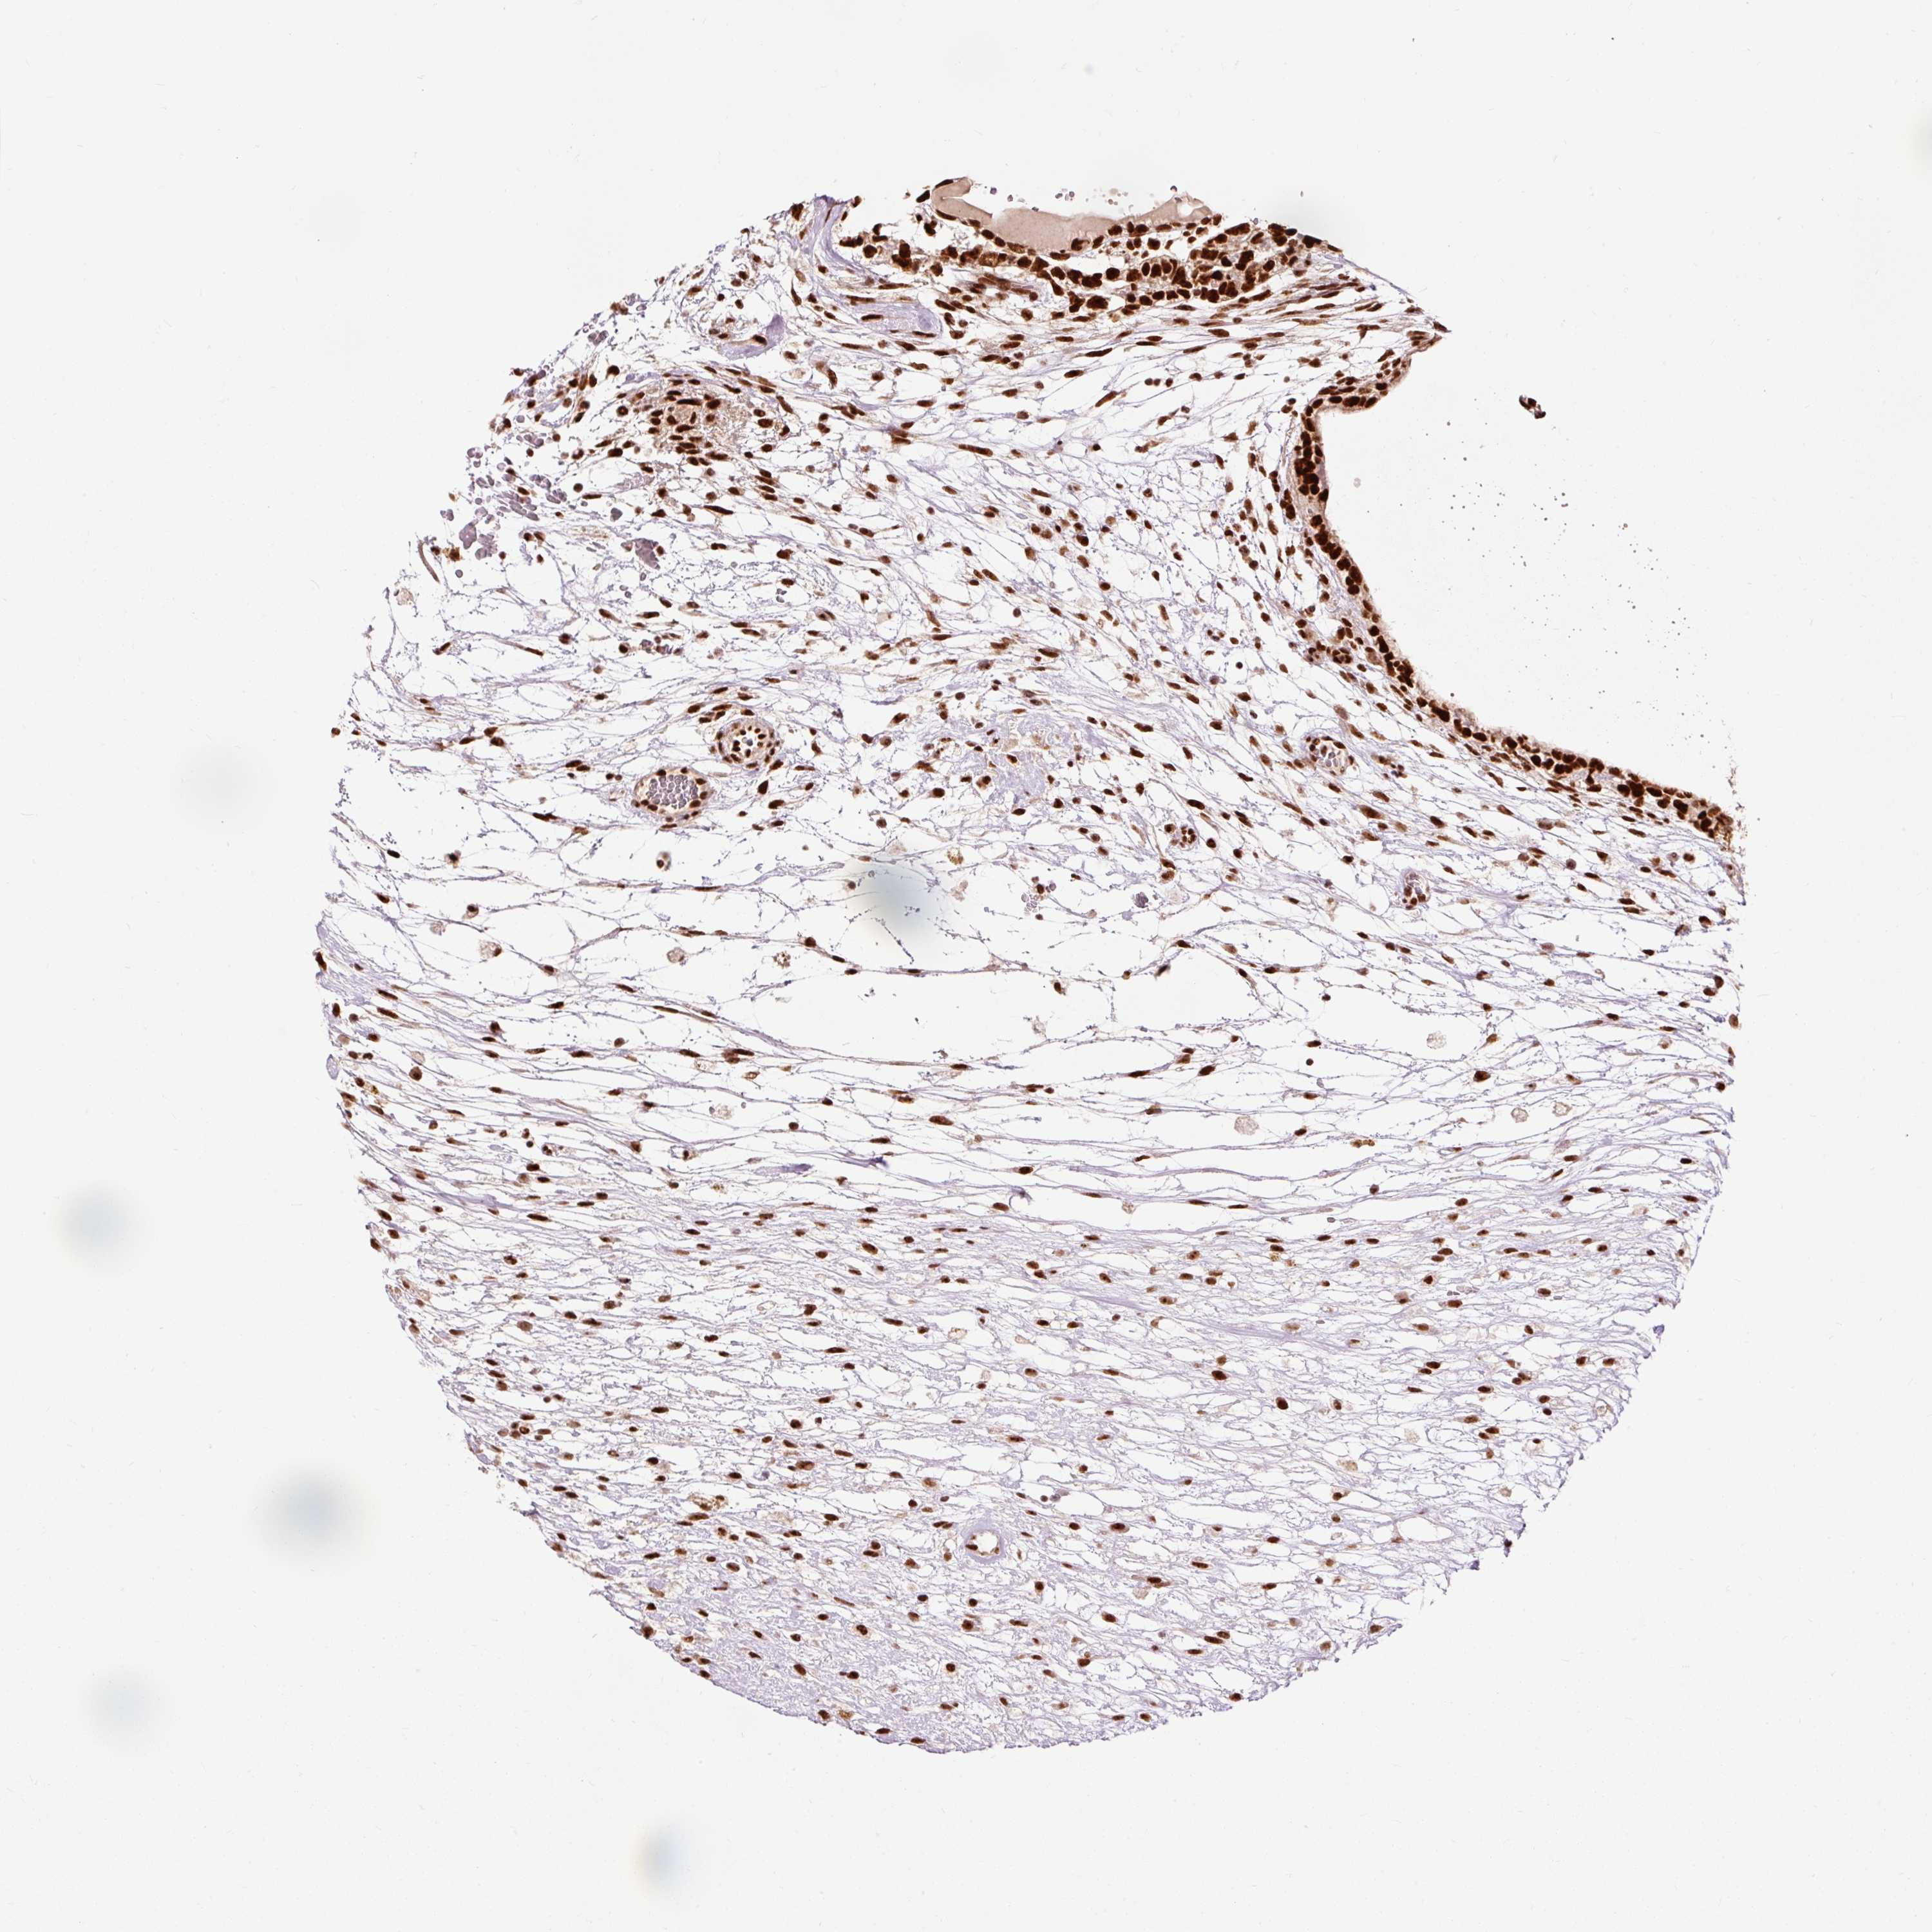

TESTIS CANCER - Protein expressioni

A mouse-over function shows sample information and annotation data. Click on an image to view it in a full screen mode. Samples can be filtered based on level of antibody staining by selecting one or several of the following categories: high, medium, low and not detected. The assay and annotation is described here.

Note that samples used for immunohistochemistry by the Human Protein Atlas do not correspond to samples in the TCGA dataset.

Antibody stainingi

Antibody staining in the annotated cell types in the current human tissue is reported as not detected, low, medium, or high, based on conventional immunohistochemistry profiling in selected tissues. This score is based on the combination of the staining intensity and fraction of stained cells.

Each image is clickable and will lead to virtual microscopy that enables deeper exploration of all samples and also displays staining intensity scores, fraction scores and subcellular localization as well as patient and tissue information for each sample.

Antibody HPA052589

Staining

High

Medium

Low

Not detected

Intensity

Strong

Moderate

Weak

Negative

Quantity

>75%

75%-25%

<25%

None

Location

Nuclear

Cytoplasmic/membranous

Cytoplasmic/membranous,nuclear

Seminoma, NOS